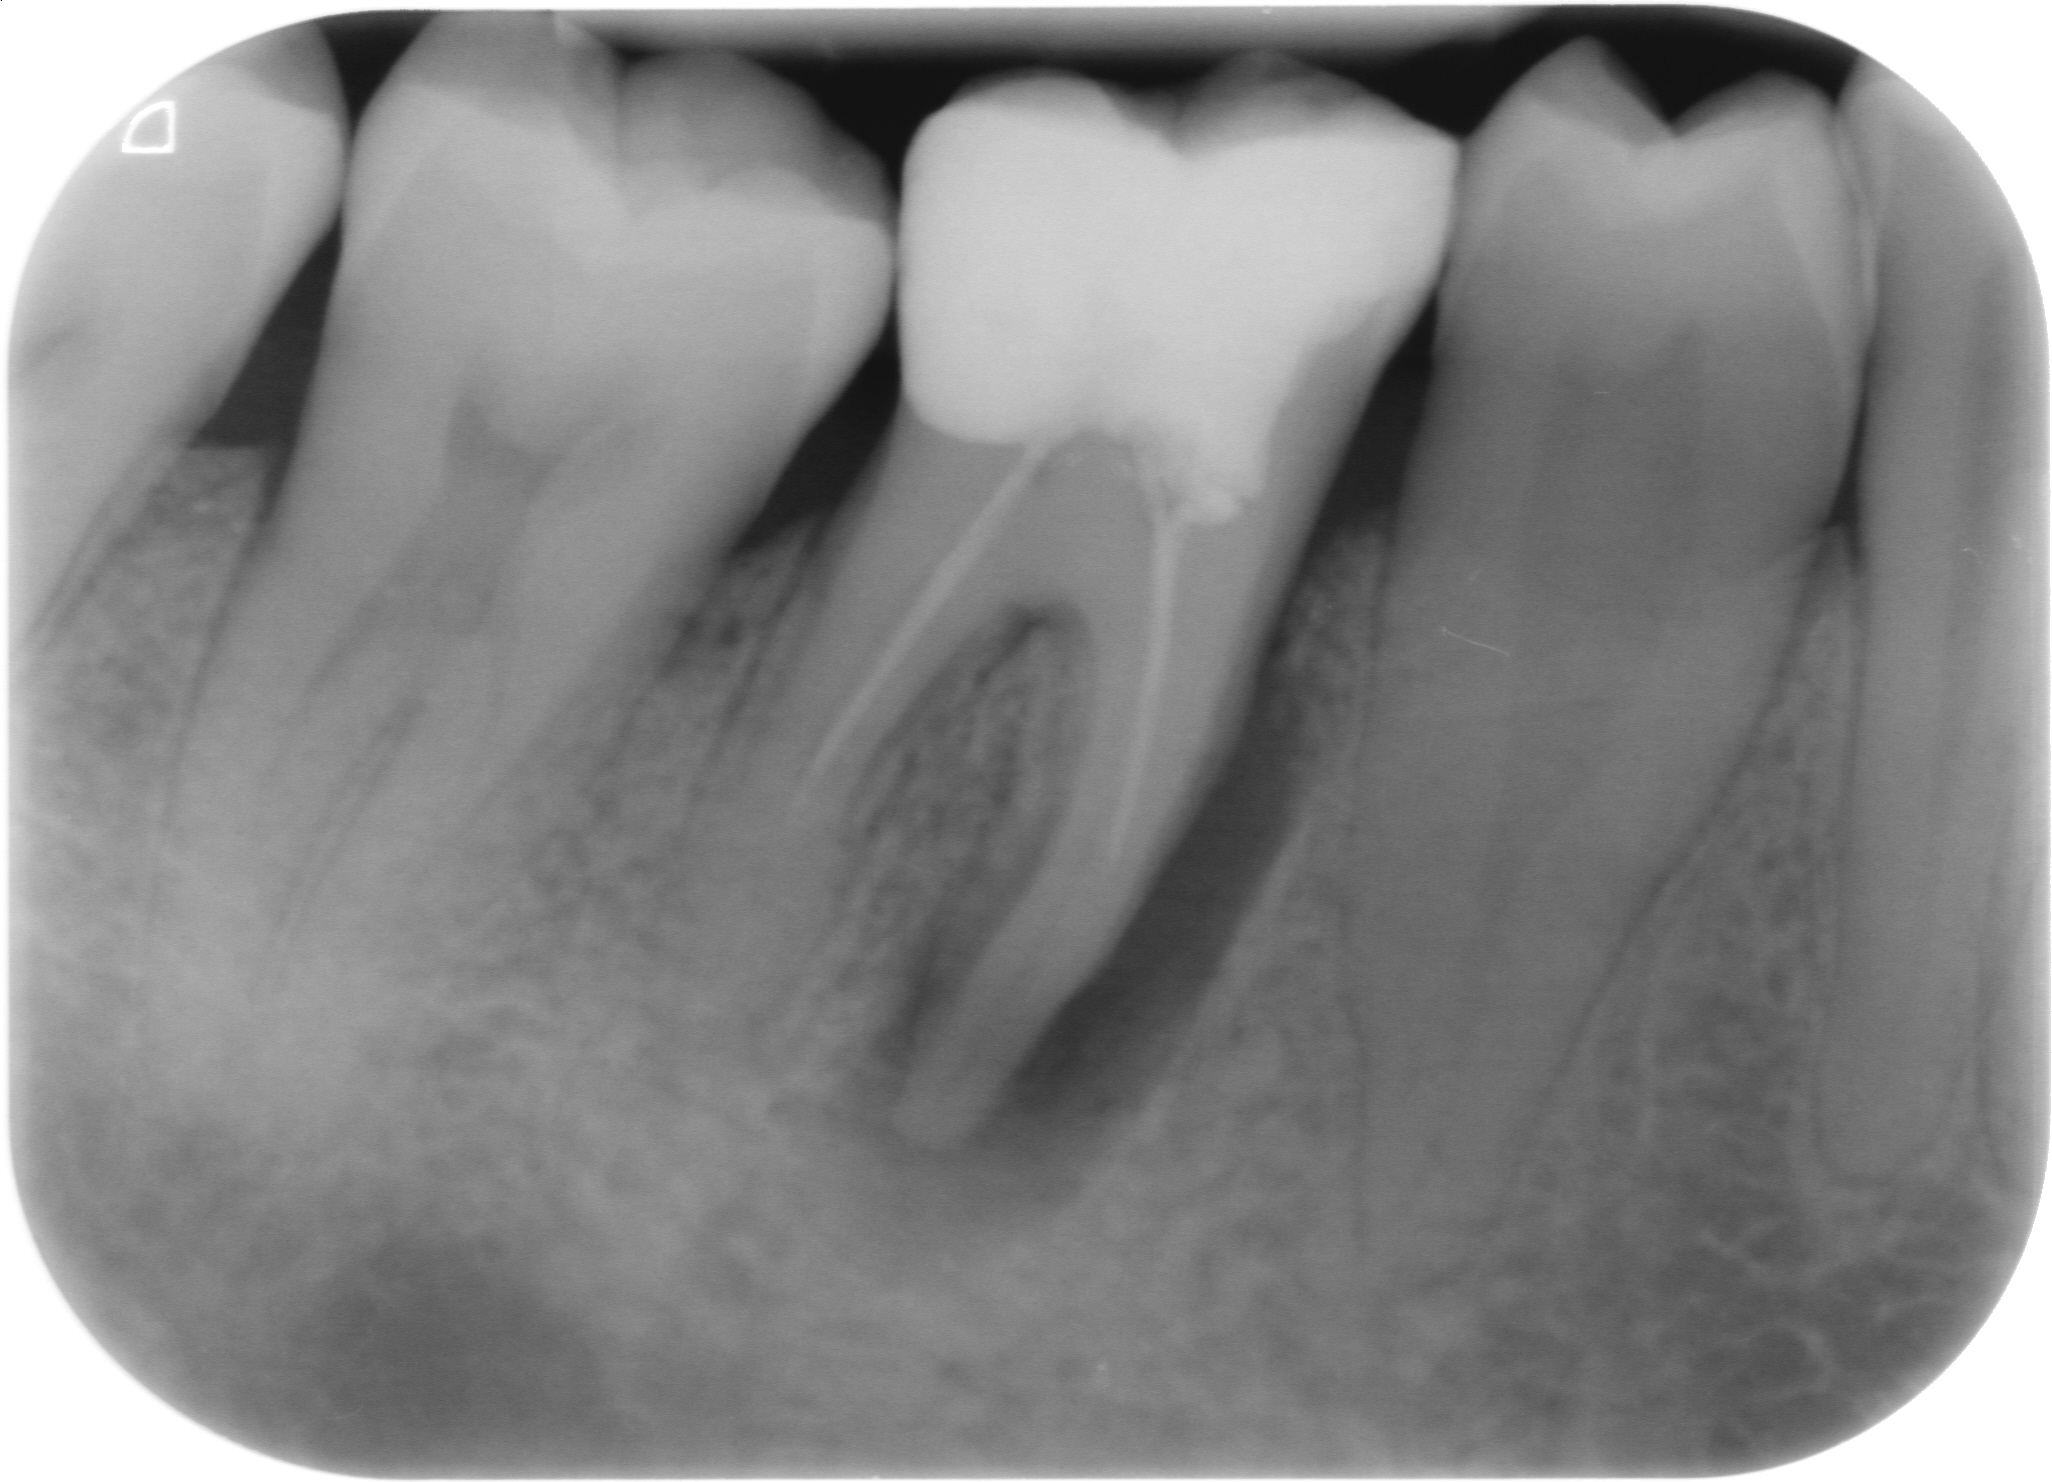

Fig. 3 : Contrôle radiographique après la finition de la prothèse.

D’un point de vue pratique, la première étape consiste à réduire les dimensions du tenon s’il occupe une grande partie de la structure coronaire, de préférence en lui donnant une forme cylindrique similaire à celle d’un tenon préfabriqué. De même, une reconstitution corono-radiculaire coulée ancrée dans plusieurs canaux doit d’abord être sectionnée jusqu’au niveau du plancher de la cavité pulpaire, afin de la traiter comme un ensemble de tenons unitaires, ce qui diminue le degré de rétention global du système. La réduction du tenon doit être effectuée avec des fraises en carbure spécialement conçues pour découper le métal, sous une irrigation abondante. Les évaluations cliniques et radiographies préliminaires sont essentielles pour planifier l’angle de coupe. La procédure doit être fréquemment vérifiée et, si nécessaire, il convient d’effectuer des contrôles radiographiques avant qu’une quantité excessive de dentine ne soit sacrifiée (Figs. 1–3).